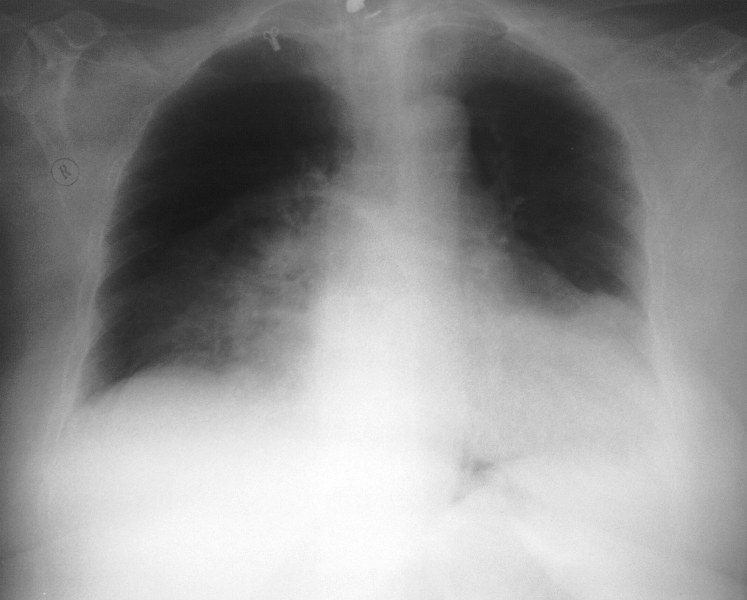

Рентгенография ОГК. Тучная пациентка с одышкой.

Справа в прикорневой зоне,на фоне инфильтрации л.ткани,очаг расспада?Корни расширены на фоне увеличеного сердца.Не плохо бы посмотреть и боковой.Но,наверное у Марио на КТ был уже ответ.Так что же было у этой пациентки?Абсцедирование?Но может быть и петля кишечника?

правосторонний пневмоторакс (справа легочный рисунок не прослеживается; коллабированное легкое) в области шеи толи артефакт то ли кальцинированный л/у но больше смущает объёмное образование больше справа в грудной клетке с горизонтальным уровнем жидкости; дала бы барий чтоб отдифференцировать(грудной желудок или дивертикул пищевода)